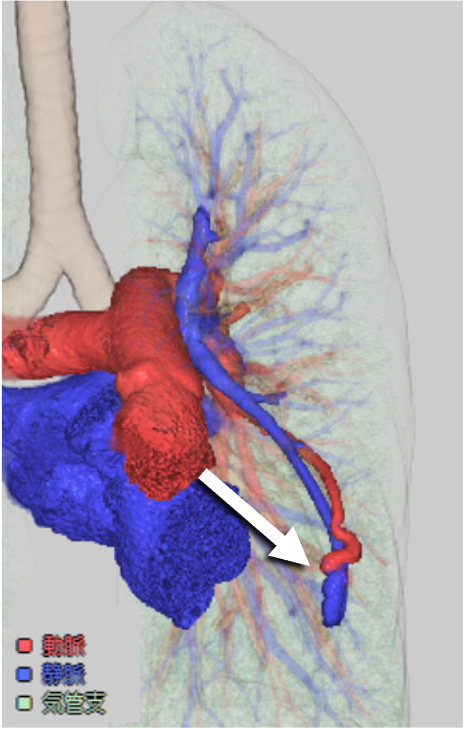

造影CTでは肺動脈と同等の強い造影効果を呈し、単純CTに比して詳細な評価が可能となる。動静脈奇形の大きさ、流入動脈・流出静脈の数や吻合の位置をあらかじめ確認することで、治療計画に有用である。また、3D画像を再構成することでより立体的に形状を把握することができ、任意の方向から画像を観察することで塞栓時のアクセスルートを決定する一助となる。